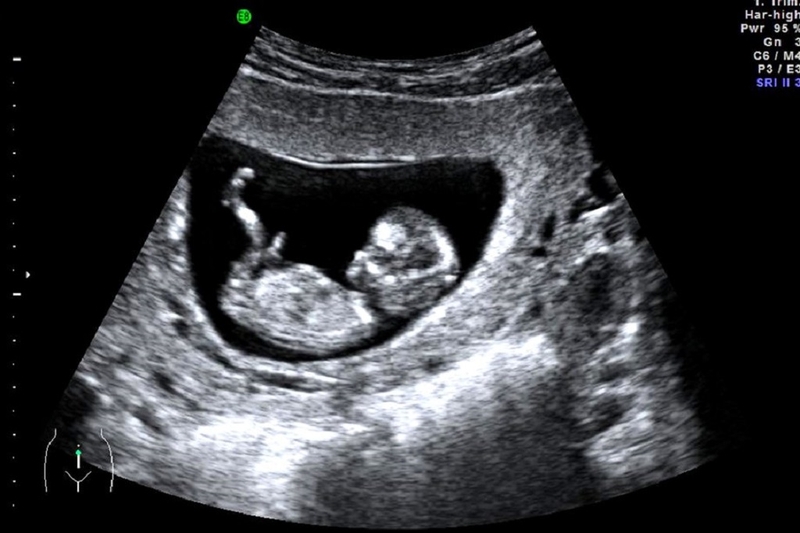

Trước khi tìm hiểu chiều dài đầu mông của em bé 12 tuần, bạn cũng nên nắm được những đặc điểm của thai nhi ở tuần 12. Siêu âm thai ở tuần thai thứ 12 là một dấu mốc quan trọng trong quá trình mang thai. Đây là thời điểm cuối tam cá nguyệt thứ nhất.

Như vậy, chiều dài đầu mông thai 12 tuần bao nhiêu là bình thường? Chiều dài đầu mông khi thai ở tuần thứ 12 thường sẽ dao động trong khoảng từ 55 - 65mm, tương đương với thai từ 12 tuần 0 ngày tới 12 tuần 6 ngày. Đặc điểm đáng chú ý nhất trong giai đoạn này là thai nhi đã bắt đầu hình thành một số phản xạ như co duỗi các ngón tay, ngón chân, miệng có phản xạ mút.

Về kích thước, thai 12 tuần sẽ có kích thước tương đương với 1 nắm tay của người lớn và cân nặng vào khoảng 15g. Chiều dài đầu mông thai 12 tuần cùng một số chỉ số khác giúp các bác sĩ chẩn đoán được tuổi thai cũng như dự phòng được nguy cơ sảy thai ở thai nhi.